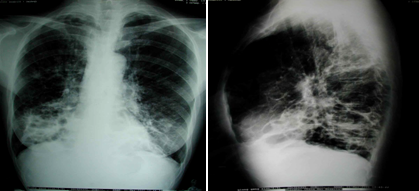

①胸部X线片

支气管柱状扩张典型的表现是轨道征,为增厚的支气管壁影。

囊状扩张特征性改变为卷发样阴影,表现为粗乱肺纹理中有多个不规则的蜂窝状透亮阴影。